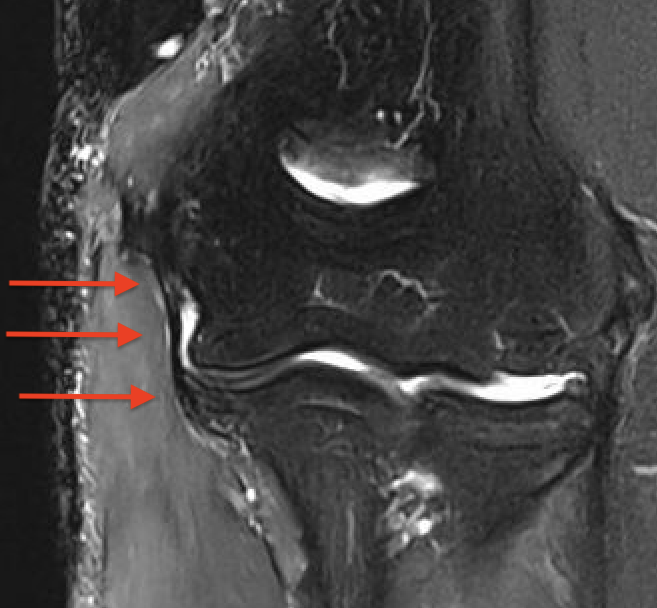

MRI

Intact

Acute full thickness UCL tear

High grade partial distal UCL tear

Bony avulsion UCL complex medial epicondyle

Bony avulsion UCL sublime tubercle